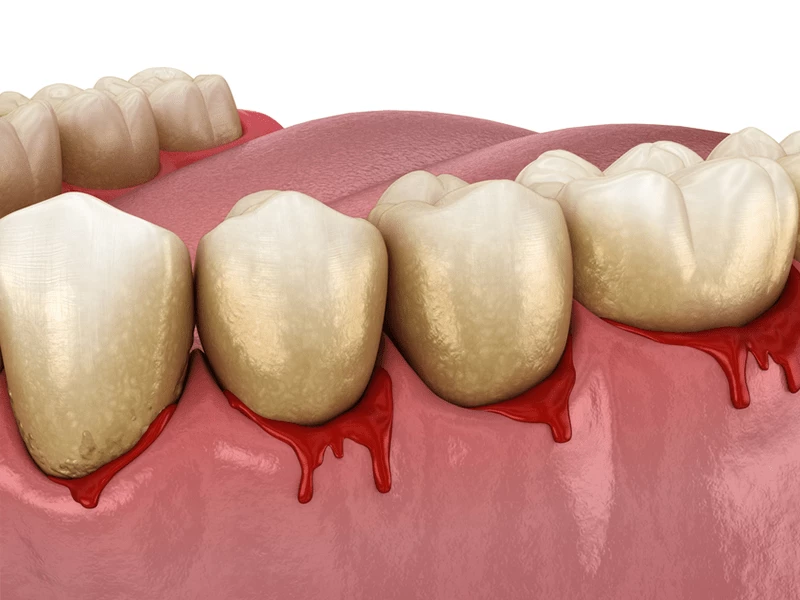

خونریزی لثه دارید؟! پس این مطلب مهم را بخوانید

خونریزی لثه نشانهای از ابتلای شما به بیماری التهاب لثه است. التهاب لثه در بین بزرگسالان نسبتا شایع بوده و نباید نادیده گرفته شود. خونریزی